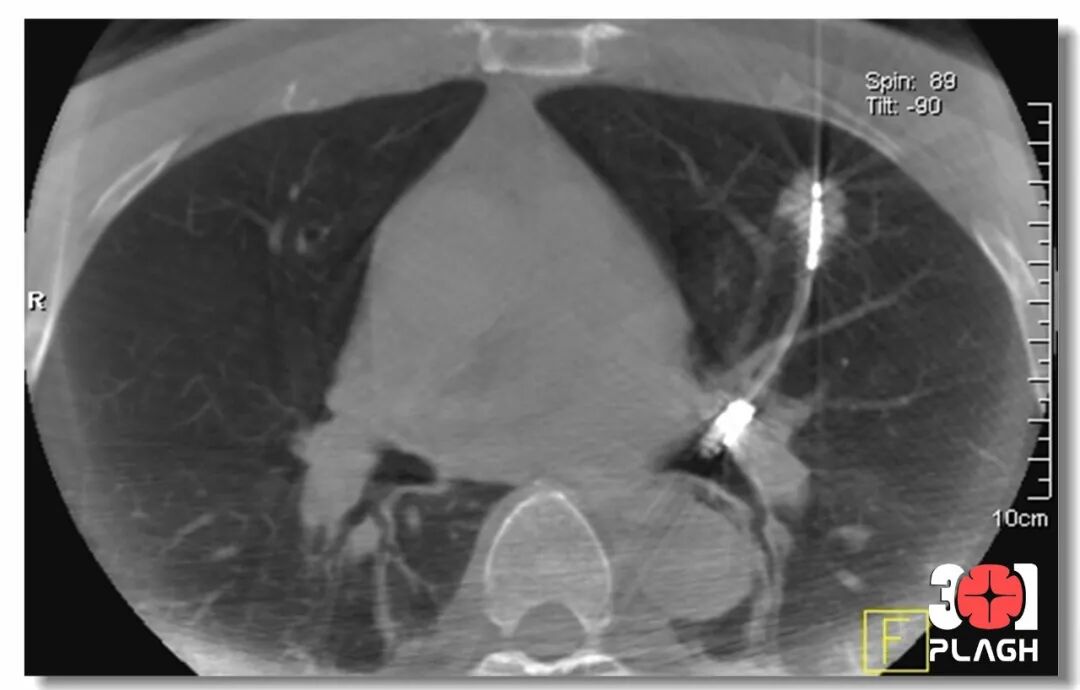

图片

▲重建CT提示消融针位于病变中央

因病变血供丰富,先由介入放射科付金鑫医生对病变进行栓塞,随后患者接受电磁导航气管镜引导下病变活检,后又进行肺结节经支气管微波消融,手术共历时60分钟,术后患者恢复好,即时复查肺部CT提示病变消融范围良好,患者无气胸、出血、发热等并发症发生。